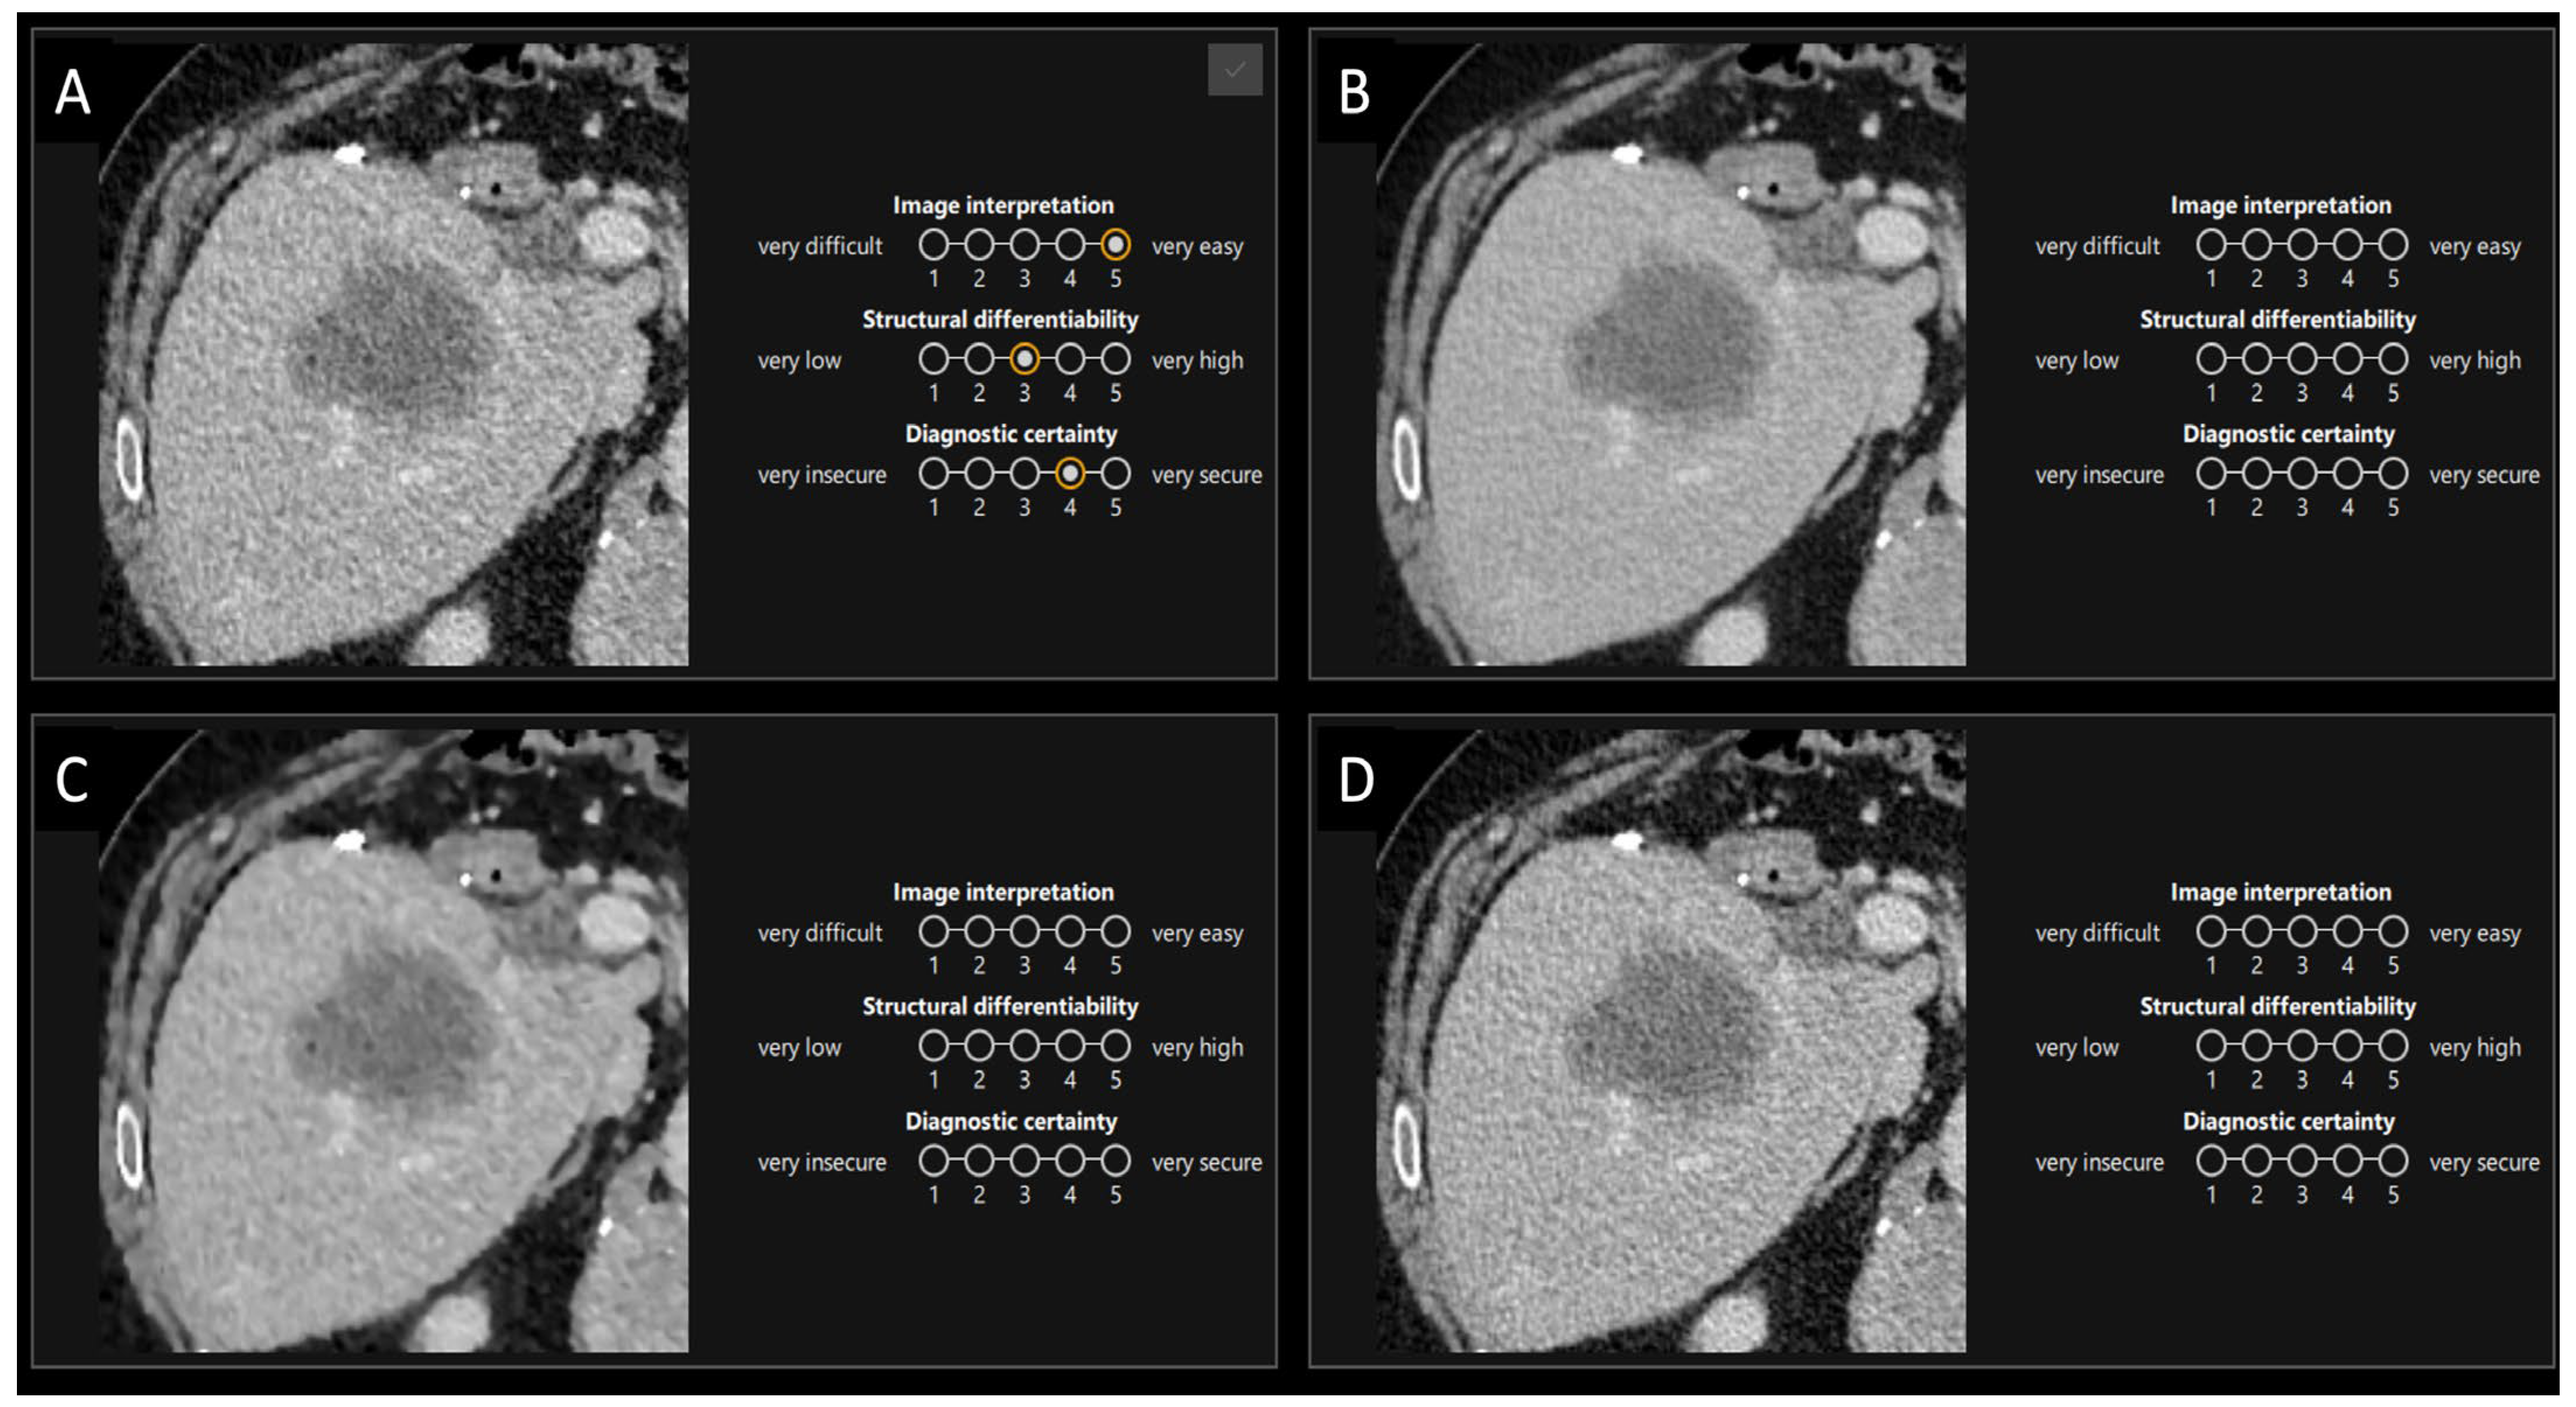

2.5.1. First Part

2.5.2. Second Part